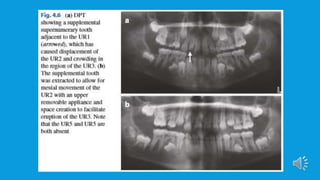

 However, if the supernumerary has interfered with normal dental devolvement

or will impede orthodontic tooth development or there’s evidence of a

pathology, then is removal should be planned. In rare cases, removal of a

supernumerary tooth may be required if its presence would otherwise

compromise alveolar bone grafting in patients with cleft lip and palate. Removal

is also indicated if the tooth is positioned at a potential implant site. In these

 Patients presenting with supernumerary teeth in the anterior maxilla associated

with failure of permanent maxillary incisor eruption and who require a general

anesthetic for removal should also have the unerupted incisor exposed and

bonded with an orthodontic attachment to facilitate guided traction.The time

frame within which the tooth will erupt is influenced by the degree of

displacement and the space available within the arch.